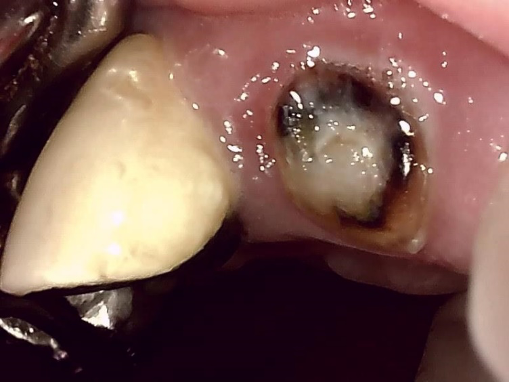

他の歯科医院で治療中です。セカンドオピニオンを希望され来院されました。むし歯が大きかったのでしょう、歯冠は削られてすでにありません。歯根のみ残っています。レントゲンでは歯根の周りに大きな歯根嚢胞が認められます。

歯根嚢胞とは、根管治療がうまくいかなかった場合根管の中の細菌が骨に侵入して骨を溶かし、歯根の周りに袋状に骨が溶けて、膿などの液体がたまる病気です。根管治療がなされていますが、根管の先端に根管治療用の針が折れて残っています。この状態では根管の細菌を死滅させることはできません。